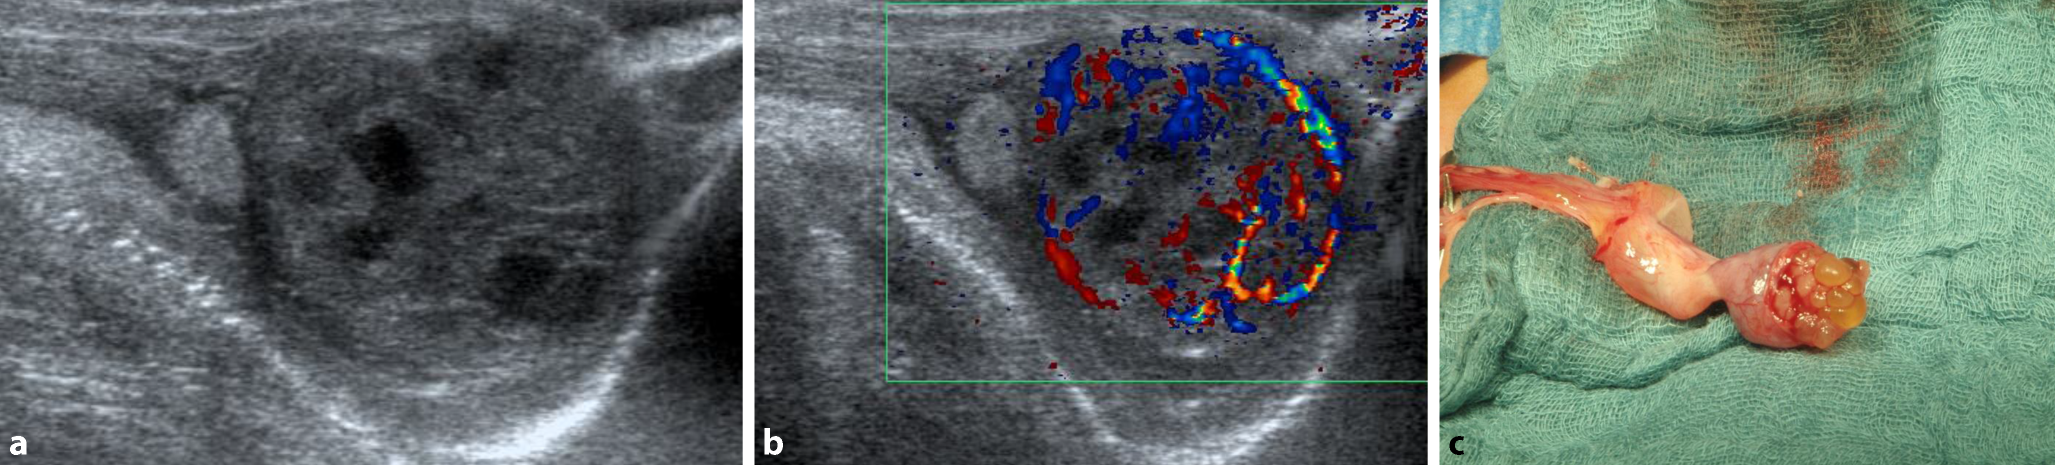

Ein männliches Neugeborenes (38 + 0 SSW, Geburtsgewicht 3600 g) wird wegen sekundären Stöhnens und Sauerstoffbedarf in die Kinderklinik verlegt. Nebenbefundlich fällt bei der Aufnahme ein prallharter linker Hoden auf. Labor: Blutbild unauffällig, Interleukin 6 erhöht, CRP zunächst im Normbereich. Im Röntgen-Thorax findet sich eine Flüssigkeitslunge. Unter dem Verdacht auf eine Neugeboreneninfektion Beginn einer parenteralen Antibiose. In der Hodensonographie (B-Bild) zeigt sich der linke Hoden orthotop mit multiplen intratestikulären Zysten im Bereich des Unterpols sowie dopplersonographisch Zeichen einer Hyperperfusion v. a. im Bereich der Hodenhüllen (Abb. 1a, b).

Abb. 1

Fall A: a Hodensonogramm (B-Bild), b Hodensonogramm (Farbduplex), c intraoperativer Befund

Bei insgesamt unklarem Befund mit nicht sicher auszuschließender peri-/postnataler Hodentorsion wird der linke Hoden notfallmäßig von inguinal operativ freigelegt. Der Hoden ist am Unterpol zystisch tumorös verändert mit multiplen, kleinen, gallertartig gefüllten Zysten ohne erkennbares Hodenparenchym (Abb. 1c). Am Hodenoberpol makroskopisch unauffälliges Hodengewebe. Der Unterpol kann in toto abpräpariert werden. Die Schnellschnittdiagnostik ergibt einen epithelialen zystischen Tumor unklarer Dignität, eine weitere Einordnung war anhand der Schnellschnitte nicht möglich. Der restliche Hoden wird daraufhin belassen und intraskrotal pexiert. Im weiteren Verlauf Beendigung der Antibiose bei unauffälligem Trachealsekret. Verlegung des Patienten am 4. postoperativen Tag auf Normalstation und Entlassung am 5. postoperativen Tag.